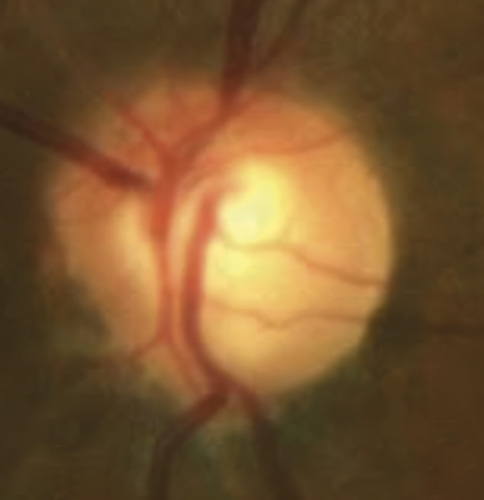

A 46-year-old African American male presents for glaucoma quarterly monitoring. Medical history is positive for hypertension controlled with 50 mg hydrochlorothiazide and reports no diagnosis of diabetes mellitus or known drug allergies. Ocular history is positive for progressive myopia bilaterally and pigment dispersion syndrome converting to pigmentary glaucoma right eye mild, left eye moderate with treatment initiated in September of 2016. The pigmentary glaucoma was treated with 0.005% latanoprost in both eyes every evening. There was positive family history of glaucoma (patient’s father). Best corrected visual acuity was measured at 20/25 in each eye. Pupillary assessment revealed a stable 1+ afferent pupillary defect in the left eye. Confrontation fields were full to finger count in the right eye and superonasal constriction in the left eye. Extraocular motilities were full with no restrictions or report of diplopia in both eyes. Slit lamp examination is remarkable for a Krukenberg spindle (Figure 4) bilaterally and a Zentmeyer line (Figure 5) in the left eye. Intraocular pressures at 3:30 pm via GAT measured 18 mmHg right eye, 23 mmHg left eye. Gonioscopy was performed and revealed open angles to ciliary body with a concave iris configuration and 4+ trabecular meshwork pigmentation (Figure 6) and the posterior corneal surface. There was no pigment attached to the anterior lens surface. The highest recorded intraocular pressures prior to treatment were 27 mmHg right eye & 35 mmHg left eye. CCT measured 554 microns in the right eye and 538 microns left eye. Optic nerve head assessment revealed bilateral intact neuroretinal rims with vertical elongation greater in the left eye than the right with inferior neuroretinal rim thinning in the left eye (Figure 7).

Bild 7: Fall 2 – (a) Sehnervenkopf OD, (b) Sehnervenkopf OS

CD ratios were estimated horizontally/vertically as 0.4/0.5 right eye, 0.6/0.8 left eye. Repeat testing of 24-2 Humphrey Visual Fields (HVF) (Figure 8) and optic nerve head optical coherence tomography (OCT) (Figure 9) were obtained.